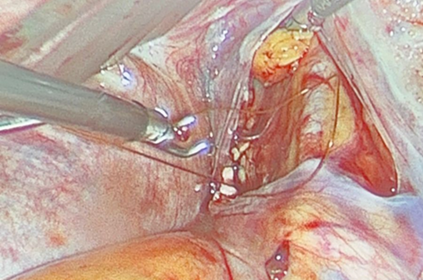

During the exploration, the right hypogastric artery was identified, locating its anterior division. Ligature was performed with 4-0 chromic suture, with no intraoperative incidents or associated injuries (Figure 3). The total estimated blood loss was 50 ml. Prior to the procedure, the fetal heart rate was 130 beats per minute; at the end, it was recorded at 140 beats per minute. The patient was transferred to the recovery area with stable vital signs, no active bleeding, and adequate peripheral perfusion.